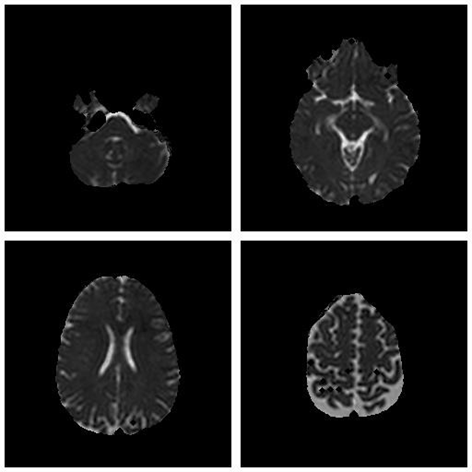

Save Image (Original Image / Clustered Image): Save only the current image to a PNG file (Figure 3). The name of the file will be the detailed title of the image.

Figure 4: 2x2 Image Result.